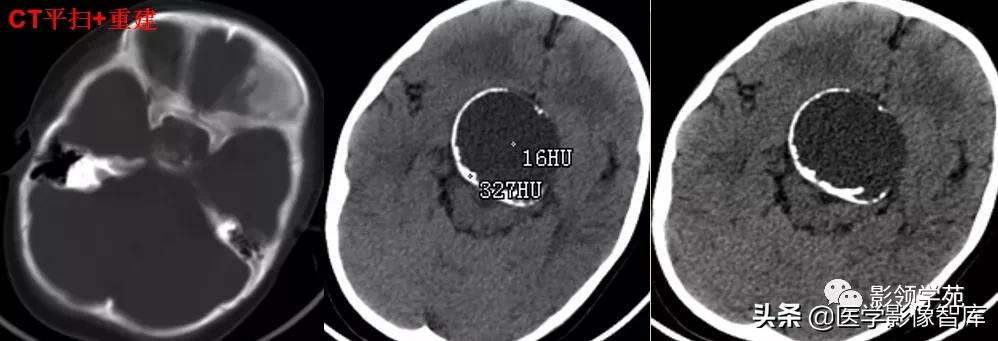

影像学表现与瘤腔内有无血栓有关:

1、无血栓者:CT平扫呈稍高密度影,增强扫描呈明显均匀强化。

2、部分血栓者:CT增强扫描,中心和囊壁明显强化--靶征。

3、完全血栓者:CT平扫呈等密度影,增强时仅囊壁强化。

女 72岁,发现糖尿病3年余

鞍上区见一团块状稍高密度影,边界尚清,密度均匀。

病灶明显强化(瘤内血栓未强化),边界清楚,与右侧颈内动脉海绵段分界不清。垂体大小、形态未见异常。